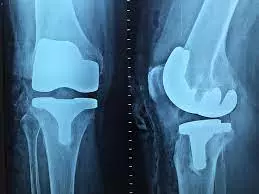

Pored operativnog lečenja meniskusa i ligamenata usluge koje pruža naša poliklinika su:

U ambulantnim uslovima izvodimo različite vrste intervencija - stopala i skočnog zgloba ruke, kolena, ramena i lakta.